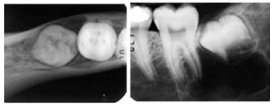

Observe a radiografia a seguir.

Qual das alternativas a seguir descreve o nome da técnica utilizada na imagem de radiografia, para a localização, vestíbulo-lingual de terceiros molares inclusos? É a técnica